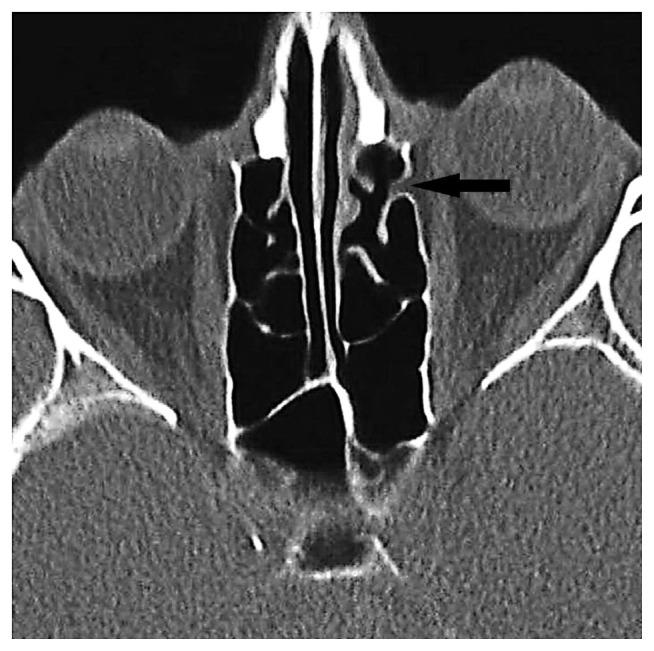

BACKGROUND/AIM: The aims of this study are to determine the incidence and more frequent localizations of orbital fat tissue herniation accompanying dehiscences in the medial orbital wall and to investigate the relationship between orbital fat tissue herniations and the anterior and posterior ethmoidal foramina.

One thousand two hundred patients who had undergone computed tomography with a preliminary diagnosis of sinusitis and who had no previous facial, orbital, paranasal sinus surgeries or history of trauma were retrospectively analyzed. The localization of the ethmoidal foramina and orbital fat tissue herniations were marked. In patients with orbital fat tissue herniation, the relationship between the localization of orbital fat tissue herniation and the anterior and posterior ethmoidal foramina was investigated.

The incidence of orbital adipose tissue herniation in our study was 7.9%. Of the 98 herniations on the bilateral medial orbital wall, 60 were in zone 3, and the most common herniation site was zone 3. A statistically significant difference was noted between the localization zone of the anterior ethmoidal foramen and the localization zones of orbital fat tissue herniations (Fisher's exact test, p < 0.001).

Zone 3 is the weakest area of the medial orbital wall, and zone 3 is the most prone to herniation of fat tissue. The association of orbital fat tissue herniations with the anterior ethmoidal foramen is extremely common. Being cognizant of this finding may help a surgeon better estimate the anatomical view to be met before functional endoscopic sinus surgery as well as to minimize the risk of possible orbital complications, especially anterior ethmoidal artery injury.

背景/目的:本研究的目的是确定眶内侧壁裂开伴发眶脂肪组织疝出的发生率及更常见的部位,并研究眶脂肪组织疝出与筛前孔和筛后孔之间的关系。

回顾性分析1200例初步诊断为鼻窦炎且既往无面部、眼眶、鼻窦手术史或外伤史的患者的计算机断层扫描结果。标记筛孔和眶脂肪组织疝出的部位。对于有眶脂肪组织疝出的患者,研究眶脂肪组织疝出部位与筛前孔和筛后孔之间的关系。

本研究中眶脂肪组织疝出的发生率为7.9%。在双侧眶内侧壁的98处疝出中,60处位于3区,最常见的疝出部位是3区。筛前孔的定位区与眶脂肪组织疝出的定位区之间存在统计学显著差异(Fisher精确检验,p<0.001)。

3区是眶内侧壁最薄弱的区域,3区最容易发生脂肪组织疝出。眶脂肪组织疝出与筛前孔的关联极为常见。认识到这一发现可能有助于外科医生在功能性鼻内镜鼻窦手术前更好地估计可能遇到的解剖情况,并将可能的眼眶并发症风险降至最低,尤其是筛前动脉损伤。